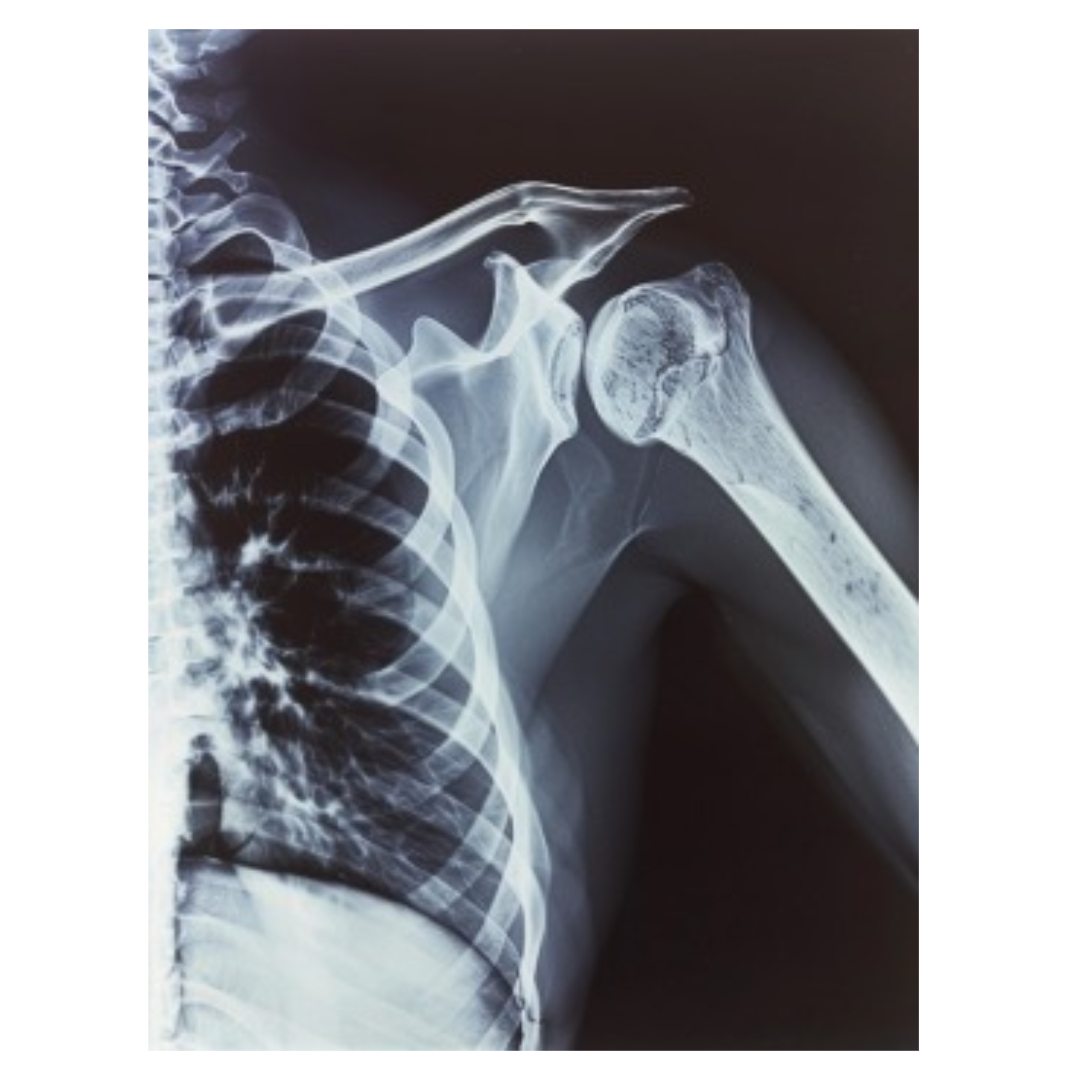

오십견 진단

오십견의 진단은 비교적 간단합니다. 의사는 환자의 증상과 신체검사를 통해 진단을 내리며, 필요시 X-ray나 MRI 등의 영상 검사를 통해 다른 질환과의 감별 진단을 시도합니다.

특히, 회전근개 파열과 같은 다른 어깨 질환과 구별하는 것이 중요합니다. 때로는 동결견의 단계에 따라 다른 접근이 필요할 수 있기 때문에, 정확한 진단이 이뤄져야 합니다.